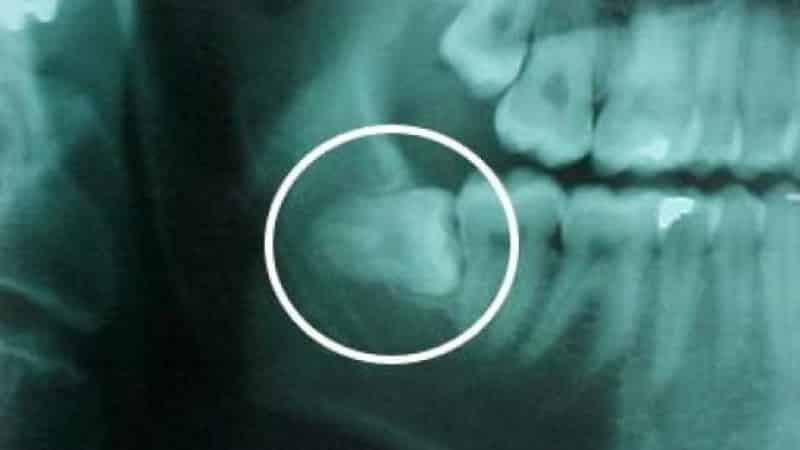

На консультации у стоматолога-хирурга вам будет проведена панорамная рентгенография третьего моляра, а при необходимости — компьютерная томография. Эти исследования необходимы для определения особенностей строения зуба, глубины расположения корня, угла наклона и других факторов.

Рентгенография

Для более точной диагностики часто требуется рентгенографическое исследование. Рентген позволяет увидеть не только положение зуба мудрости относительно соседних зубов, но и его корни, которые могут быть изогнутыми или расположенными вблизи нервных окончаний. Существует несколько типов рентгеновских снимков, включая панорамные и прицельные, которые помогают стоматологу получить полное представление о состоянии зуба и окружающих тканей.

Компьютерная томография

В некоторых случаях, особенно если рентгенография не дает достаточной информации, может быть назначена компьютерная томография (КТ). Этот метод позволяет получить трехмерное изображение зуба мудрости и окружающих структур, что особенно полезно при планировании хирургического вмешательства. КТ помогает выявить возможные осложнения, такие как близость зуба к нижнечелюстному нерву.